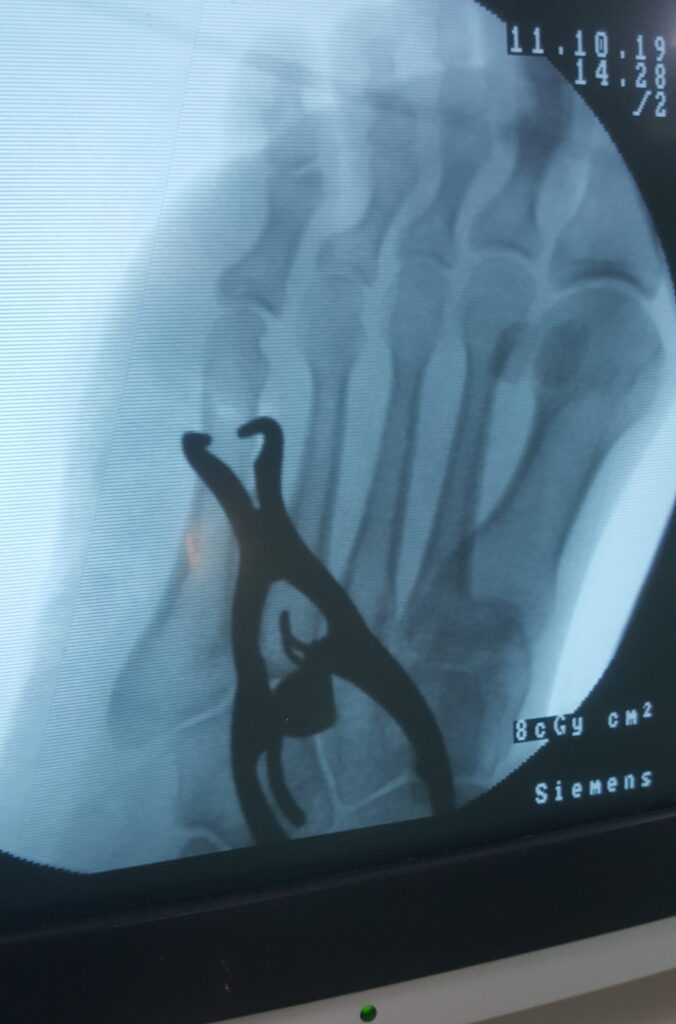

Percutaneous Pinning

This method involves thin wires or pins placed through the skin. It is used for wrist, hand, or finger fractures. Dr. Imran Salim Malik uses this to avoid large cuts and reduce healing time.